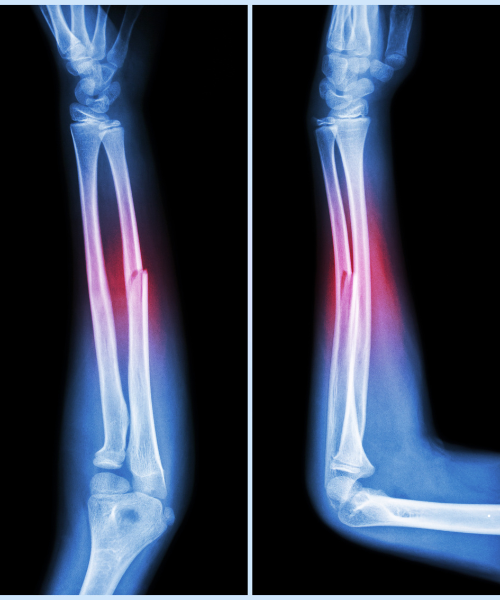

Complex Trauma & Fracture Management

Dr. S.P. Modanwal is a skilled orthopedic surgeon in Varanasi specializing in complex trauma and fracture management. He provides advanced treatment for severe bone injuries using modern surgical techniques for faster recovery and lasting mobility. Known for his precision and compassionate care, Dr. Modanwal is a trusted name in orthopedic trauma care in Varanasi.